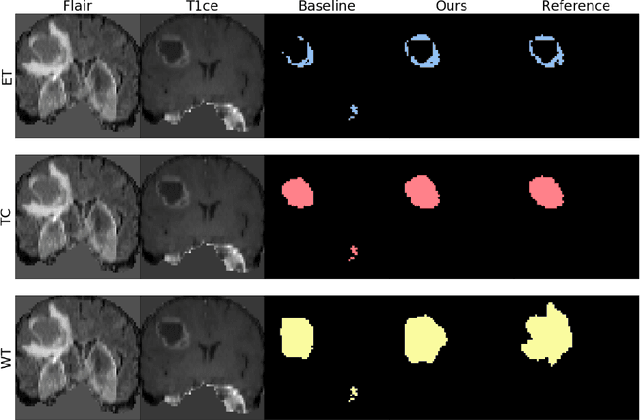

Abstract:The joint use of multiple imaging modalities for medical image segmentation has been widely studied in recent years. The fusion of information from different modalities has demonstrated to improve the segmentation accuracy, with respect to mono-modal segmentations, in several applications. However, acquiring multiple modalities is usually not possible in a clinical setting due to a limited number of physicians and scanners, and to limit costs and scan time. Most of the time, only one modality is acquired. In this paper, we propose KD-Net, a framework to transfer knowledge from a trained multi-modal network (teacher) to a mono-modal one (student). The proposed method is an adaptation of the generalized distillation framework where the student network is trained on a subset (1 modality) of the teacher's inputs (n modalities). We illustrate the effectiveness of the proposed framework in brain tumor segmentation with the BraTS 2018 dataset. Using different architectures, we show that the student network effectively learns from the teacher and always outperforms the baseline mono-modal network in terms of segmentation accuracy.